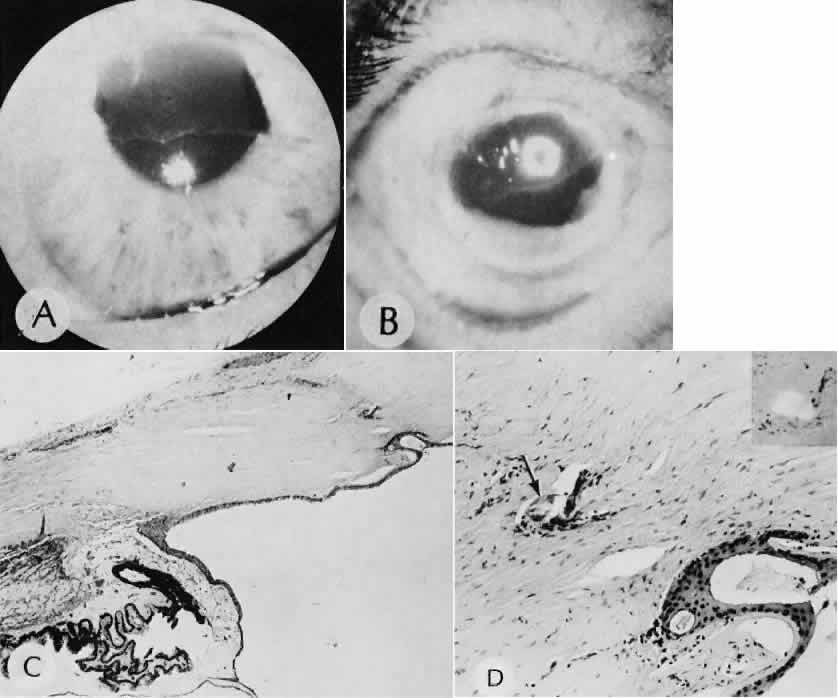

Cyclocryotherapy, cyclodiathermy (Fig. 20), and therapeutic ultrasonography apply energy directly to the pars plicata and cause lysis of the ciliary muscle and occlusion of the vascular supply, leading to extensive necrosis and scarring. Pressure lowering is accomplished by a reduction of aqueous production. Heat applied to the sclera may cause necrosis and localized scleral thinning. Cold applied to the sclera, unless extreme, does not cause any clinical or histologic changes.

Fig. 20. Cyclodiathermy treatment of the ciliary body to control glaucoma. A. Gross photograph illustrates extensive areas of depigmentation mainly in the region of the pars plana (arrows) rather than the pars plicata. B. Light micrograph of the region of the pars plana illustrates an extensive area of tissue degeneration of the pars plana (between arrows) in the late postoperative course. C. Light micrograph of the destructive effects of cyclocryotherapy also in the region of the pars plana and pars plicata. The ciliary epithelium in the early postoperative period is necrotic and cystic. (Hematoxin-eosin stain; A, × 8; B, × 16.)